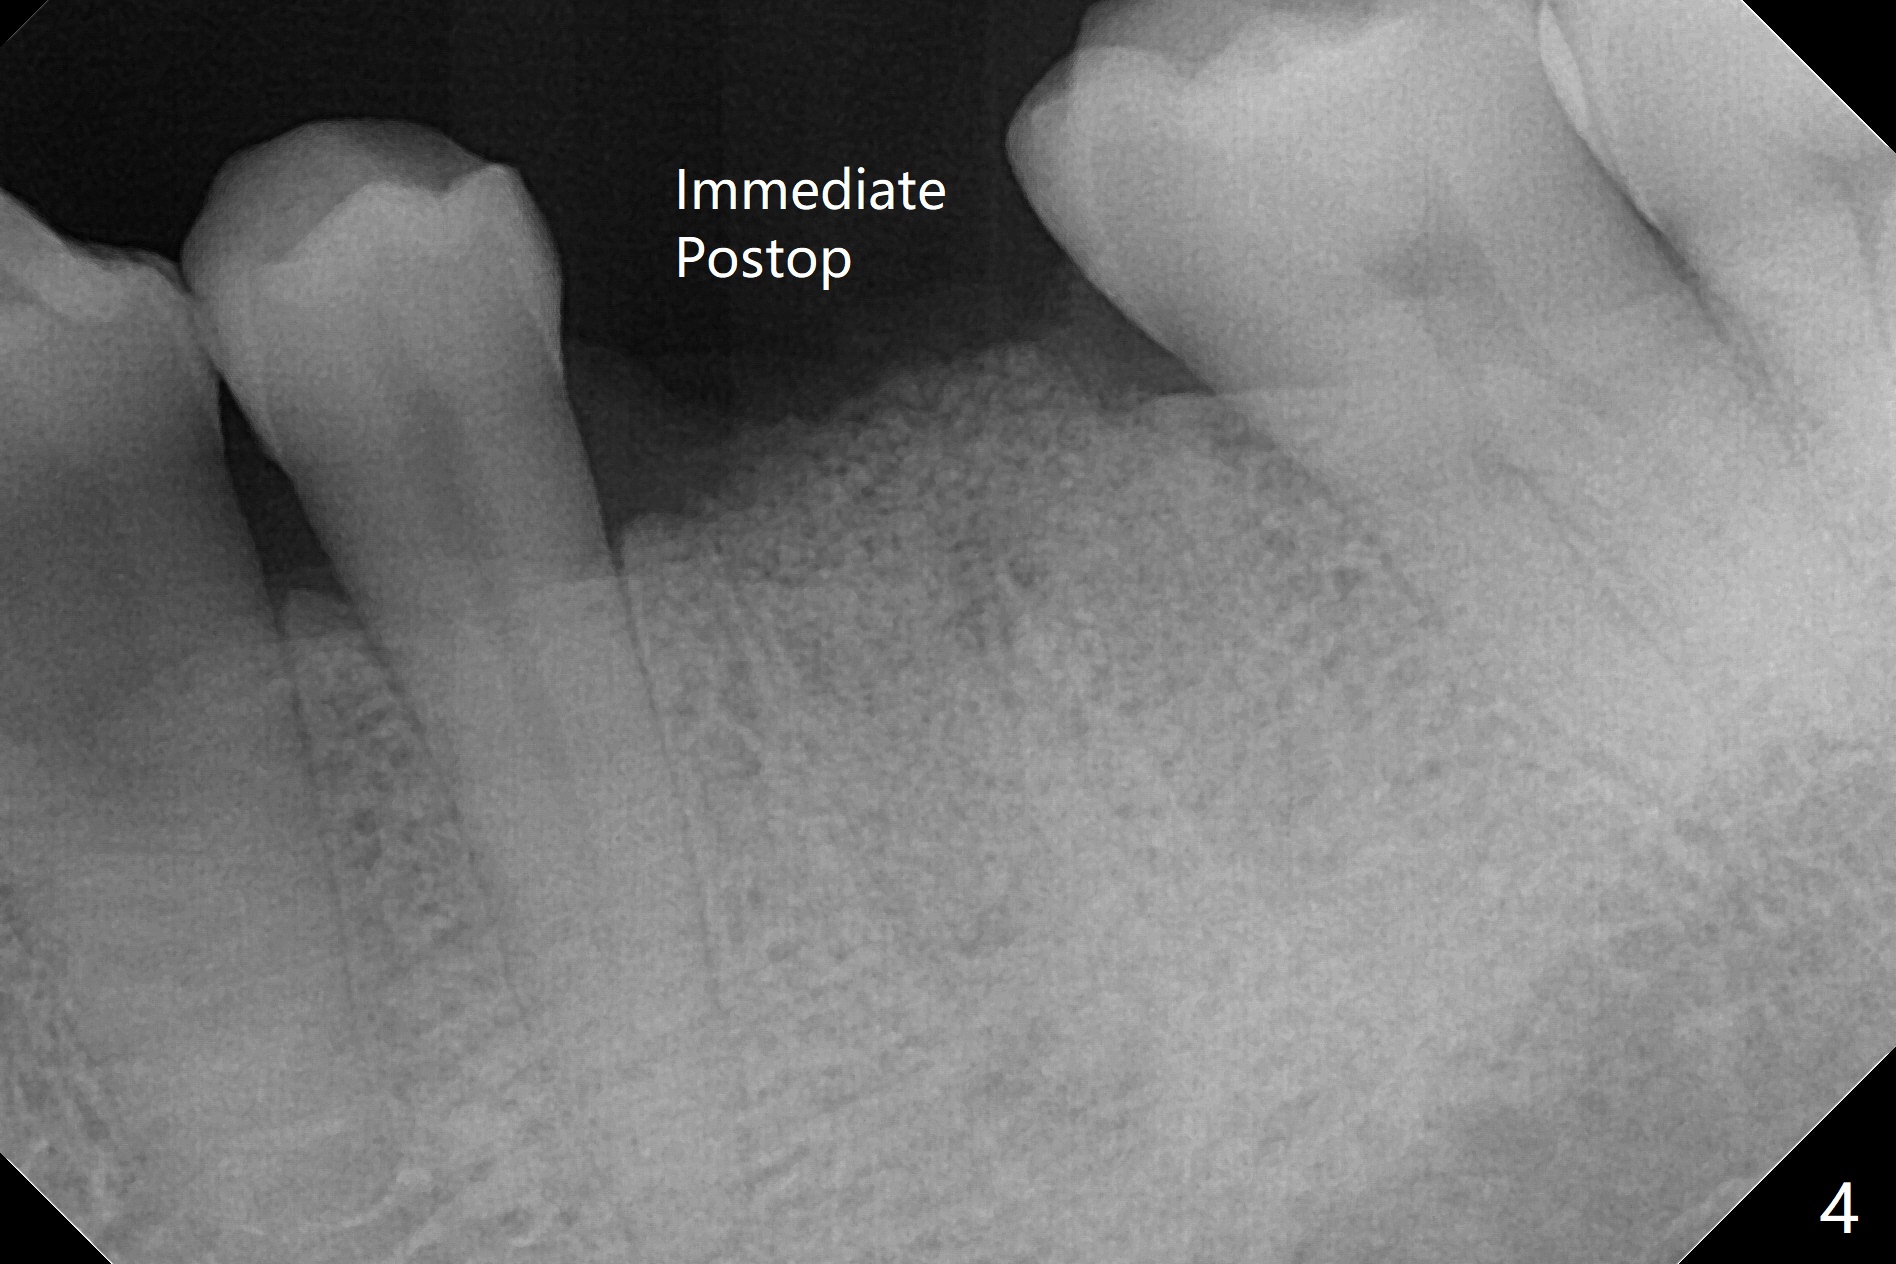

When the patient returns for #15 comp, the bone resorption and swelling at #19 are worse than those 3 years ago (Fig.1,2). After debridement, the mesial socket is large, while the septum is thin, irregular and with undercut (Fig.3). It seems difficult to obtain primary stability for an immediate implant. Vanilla bone and cortical bone hydrated with GEM21 S are placed for socket preservation (Fig.4,5), followed by 12x12 mm BioXclude and 4/0 PGA. In fact the bone height is limited for an immediate implant (Fig.6 (5x10 mm)). There is not enough bone in the septum for primary stability (Fig.7 (cross section of 3D image; L: lingual)). The socket heals 16 days postop (Fig.8). It appears that the granulation tissue is covered by a thin layer of granulation tissue (Fig.9 *), while the membrane remains in place (M). In fact the bone graft remains in the soft tissue zone as well as the hard tissue one (Fig.10). In spite of no apparent loss of bone graft (Fig.4,10), the graft seems to shrink in height 3.5 months postop (Fig.11), while the crest decreases (compare Fig.1 and 11). The keratinized gingiva is wide, but the alveolus reduces in width (Fig.12). The buccal crestal bone is lost 3.5 months postop (Fig.13).